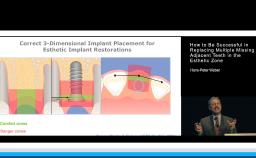

This lecture analyzes the impact of key risk factors on esthetic outcomes with implant restorations in the anterior maxilla. It provides a standardized way of collecting pertinent clinical and radiographic data and presenting them to the patient in order to form realistic treatment expectations. This presentation stresses the importance of prosthodontically driven implant positioning by respecting the ‘comfort zones’ and avoiding the ‘danger zones’. It recommends practical chairside procedures for shaping natural emergence profiles with the help of provisional implant restorations and then conveying this information to the dental laboratory by fabricating customized impression copings. Finally, this lecture stresses the importance of original-on-original components to avoid future mechanical and biological complications.

- recognize the importance of prosthodontically driven implant positioning in avoiding poor esthetic outcomes

- recognize the necessity of provisional implant restorations in the shaping of natural-looking emergence profiles